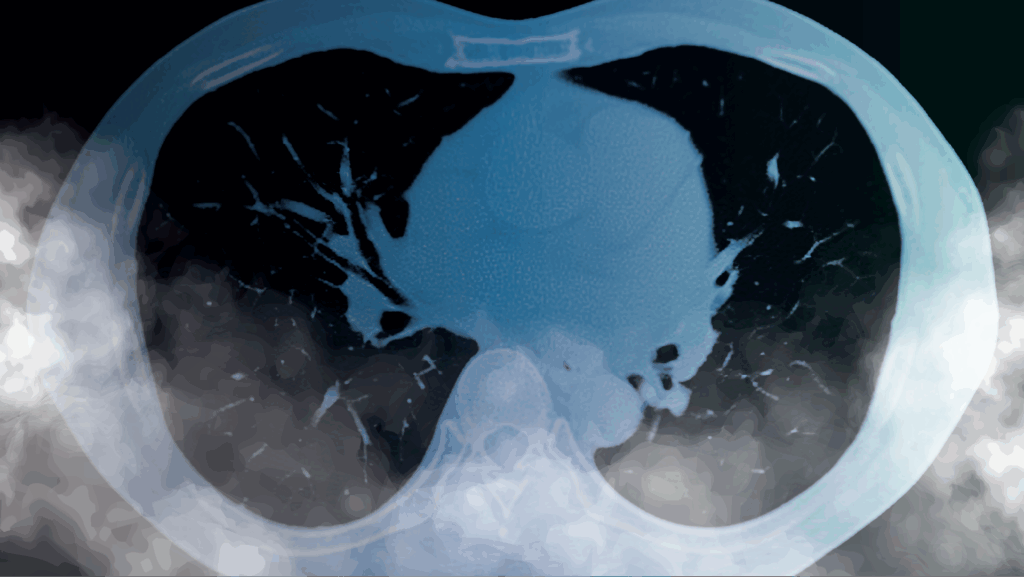

A Chest CT scan is a vital imaging test that creates highly detailed pictures of your lungs, heart, blood vessels, and other structures inside your chest. At Chest Scan Australia, we specialise in Low Dose Chest CT scans to deliver clear results while keeping your radiation exposure as low as possible.

Lung cancer can be hard to detect in its early stages. Symptoms may be vague or even absent. If your doctor suspects lung cancer, they will order a series of tests to help make a diagnosis.